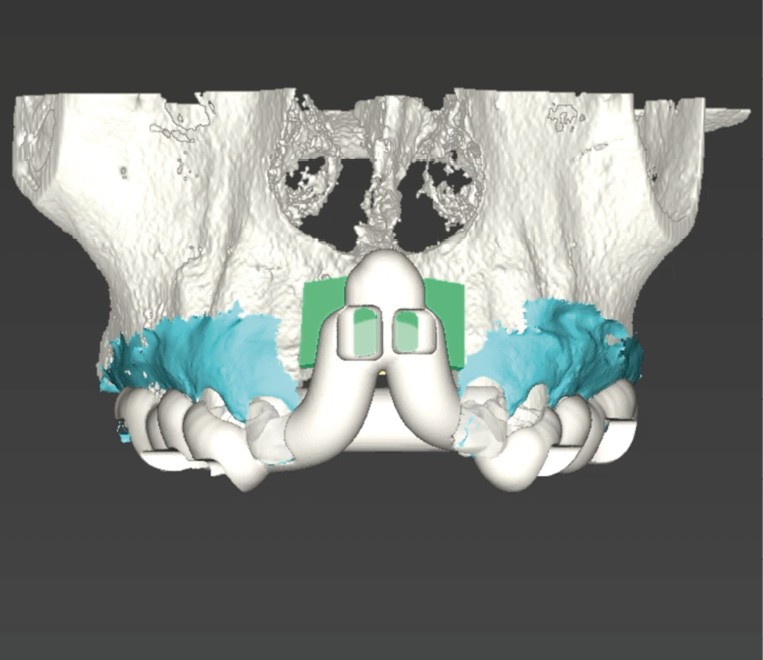

L’avènement des technologies numériques a permis d’améliorer la précision de ces procédures. La planification implantaire 3D, associée à la conception et fabrication assistée par ordinateur (CAD/CAM), permet aujourd’hui de concevoir des guides chirurgicaux spécifiques optimisant et sécurisant le positionnement des blocs osseux. De même, la démocratisation récente des techniques de chirurgie guidée dynamiques par caméra stéréoscopique constitue un outil attractif pour les techniques de reconstruction osseuse. Ainsi, la taille du bloc à prélever sur la zone rétromolaire mandibulaire peut aussi être exactement déterminée en amont de la chirurgie (fig. 1 et 2).

La chirurgie guidée dynamique permet, quant à elle, de prélever par piezochirurgie (Piezotouch, Mectron) de façon naviguée (fig. 3). Ainsi, le bloc peut être designé en amont sur le logiciel de planification implantaire pour correspondre parfaitement au défaut osseux en présence, et prélevé à l’identique sur la ligne oblique externe (fig. 4 à 8).